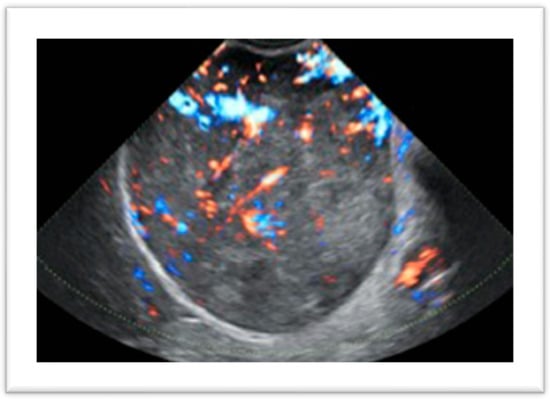

The diagnosis of uterine fibroids is primarily based on imaging techniques. Frequently, myomas are detected incidentally during transvaginal sonography (TVS) in asymptomatic or symptomatic patients. Ultrasound is the first-line imaging technique in the diagnosis of uterine leiomyomas because of its wide availability, non-invasiveness, and low cost [28]. The aim of TVS, as well as other imaging techniques, is to detect the presence of myometrial lesions, to evaluate the dimensions and localization of each lesion and to assess their nature, excluding differential diagnoses such as adenomyosis, smooth tumors of unknown malignant potential (STUMPs) and leiomyosarcomas, although the final diagnosis is only anatomopathological. Depending on patient preference and uterine dimensions, ultrasound pelvic assessment can be performed using transvaginal or transrectal probes, or alternatively through transabdominal scanning, which is preferred in virginal patients or in cases of subserosal or voluminous fibroids extending beyond the small pelvis that otherwise cannot be well evaluated. The ultrasonographic characteristics of leiomyomas are well defined in the literature, and the first accurate description of the ultrasonographic features of fibroids was published in 2015 in the MUSA (Morphological Uterus Sonographic Assessment) consensus [29]. They appear as rounded solid lesions with well-defined margins and internal fan-shaped shadows. In some cases, calcifications may be present, appearing as hyperechoic areas within the lesion, or the internal content may be inhomogeneous due to lipomatous or ialine degeneration. The use of color or power Doppler gives additional information about the vascularization of the lesions, and usually myomas present a peripheral vascularization and a rare and scarce internal blood flow. This feature is of particular interest in the differential diagnosis of benign and malignant lesions, as the latter tend to have a central distribution of vessels even though there are some exceptions (Figure 1).

Figure 1.

Uterine leiomyoma with atypical vascular features.

In a recent study, Russo et al. [28] put in correlation the ultrasonographic characteristics of highly vascularized uterine fibroids with their histopathological diagnosis. The authors found that of 70 fibroids with extensive central vascularization, 7% were sarcomas, highlighting that the vascular pattern is a strong risk factor for malignancy, but a central flow was also present in 93% of lesions of a benign nature making the differential diagnosis challenging and requiring additional criteria to determine the nature of the findings. Elements that need to be assessed include patient age, number of lesions, borders, and ultrasound features. Myomas generally have regular borders and are more likely to be multiple, while a single lesion with inhomogeneous echogenicity is more likely to be malignant. Cystic areas are confounding features as they can be present in both cases, and are presumed to be due to necrosis. Russo et al. [28] found this characteristic in 31.3% of typical leiomyomas, in 55.2% of leiomyoma variants as myxoid, and in 40% of malignant lesions. On the other hand, the presence of calcifications and shadowing are considered reassuring features, as they are generally not present in malignant lesions. In a recent study, De Bruyn et al. [30] confirmed that sarcomas more often show an irregular shape, with non-uniform echogenicity, cystic areas and necrosis, and are highly vascularized, while calcifications are generally absent, as described above. Once the presence of myomas has been identified, the second step is to correctly describe their position in the myometrium and their relationship to the endometrial cavity and serosa according to the FIGO classification system [21]. In the preoperative view, this aspect is fundamental for planning an accurate and tailored surgery. Submucosal fibroids (i.e., FIGO 0-1-2) require a hysteroscopic approach. In these cases, the intracavitary portion needs to be measured and further information on the myometrial-free margin to the serosa is useful for precise surgical planning. For this reason, two possible techniques can be added to 2D TVS: saline contrast sonohysterography (SHG) and 3D TVS, which are becoming valid alternatives to diagnostic hysteroscopy (Figure 2).